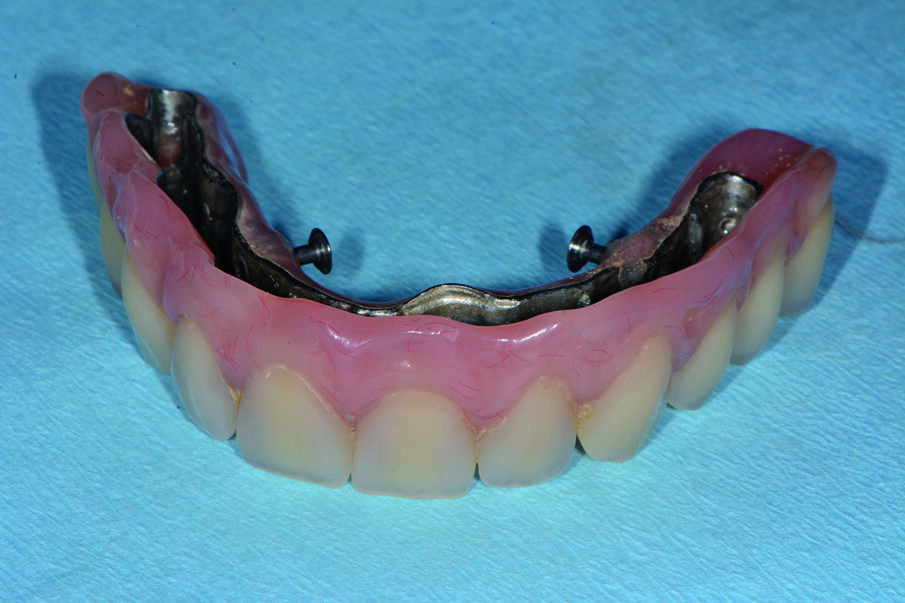

Dopo la terapia chirurgica, si inserisce una protesi totale provvisoria, che il paziente porterà per 6 mesi (Fig. 4b). Dopo i 6 mesi si monta la barra e la protesi totale superiore (Figg. 5, 6), che oltre a migliorare la masticazione e la fonetica del paziente, supporterà anche i tessuti molli, labbro, guancia, ridando al paziente un aspetto del sorriso giovanile e un supporto dei tessuti molli orali delle labbra, delle guance e delle rughe geniene (Figg. 7, 8). Il paziente viene inserito in un piano di mantenimento con un follow-up ogni 3 mesi (Fig. 9).

Igienizzazione del manufatto protesico

Dopo aver condiviso con il paziente la presenza del biofilm batterico sul manufatto protesico, immergiamo la protesi nel pulitore ad aghi Sympro, dopo aver riempito l’apparecchio con 200 ml di Fluid Sympro Universal, chiudiamo e scegliamo la modalità di 2000 giri/minuti per 15 minuti. Un campo magnetico rotante mette in movimento gli aghi di pulizia che asportano i depositi dalla superficie con una delicata azione meccanica. Al termine con la pinzetta preleviamo il manufatto protesico e sciacquiamo ripetutamente. L’azione sinergica del fluido detergente e dell’apparecchio ad aghi ha rimosso in modo rapido ed efficace il biofilm batterico e i depositi di tartaro. Sui siti con una ritenzione di biofilm batterico maggiore viene eseguita la remineralizzazione dei tessuti a rischio (Figg. 16a-16c).